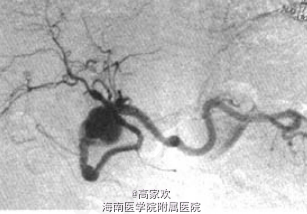

查体:心肺腹查未见明显异常。 腹部CT示:胰头部类圆形低密度影。 血管造影示:肠系膜上动脉与胃十二指肠动脉吻合支明显增粗。见巨大动脉瘤,直径为25~27 mm,远端见肝动脉、脾动脉显影。 其余实验室检查未见明显异常。

诊断:胃十二指肠假性动脉瘤 处理:采用Seldinger法,经右侧股动脉穿刺插管,将5F肝动脉导管插入腹腔动脉内造影,肝动脉未显示;将导管插入肠系膜上动脉造影,可见右副肝动脉。肠系膜上动脉与胃十二指肠动脉吻合支明显增粗。见巨大动脉瘤,直径为25~27mm,远端见肝动脉、脾动脉显影。将导管插入动脉瘤远端血端血管内用8mm、5mm。钢圈栓塞后,将导管退致动脉瘤近端血管内,用明胶海绵颗粒填塞动瘤。再用5mm钢圈拴塞。栓塞后造影示动脉瘤未显影。